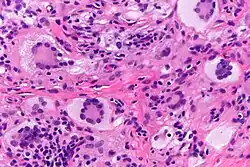

Touton giant cells are named for Karl Touton, a German botanist and dermatologist.[3] Karl Touton first observed these cells in 1885 and named them "xanthelasmatic giant cells", a name which has since fallen out of favor.[4] Karl Touton observed these giant cells when examining a biopsy or skin tissue sample from someone with a lesion under a microscope. He then classified and named these cells due to their strikingly unique appearance. Touton giant cells are still observed using these methods as well as staining with histological dyes such as hematoxylin and eosin (H&E).[5]

Touton giant cells, being multinucleated giant cells, can be distinguished by the presence of several nuclei in a distinct pattern. This pattern is described as a ring-like or wreath-like in the center of a cell. These cells contain a ring of nuclei surrounding a central homogeneous cytoplasm, while foamy cytoplasm surrounds the nuclei.[6][7] The cytoplasm is usually lipid-rich and has a foamy appearance. The cytoplasm is divided into two distinct areas: the peripheral zone and the central zone. The central zone is the cytoplasm surrounded by the nuclei which is described as both amphophilic and eosinophilic. Meanwhile, the cytoplasm near the periphery of the cell, the peripheral zone, is pale and contains vacuoles due to the lipid content in this zone of the cell.[1][8]